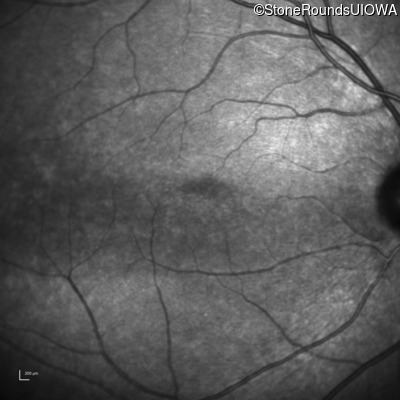

Congenital Stationary Synaptic Dysfunction (IA2g)

Congenital Stationary Synaptic Dysfunction (IA2g)

| Congenital Stationary Synaptic Dysfunction | CABP4 | Arg49Stop CGA>TGA | IVS1+1 G>T | AR |